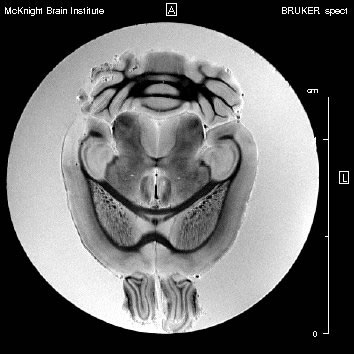

SAIP(Small-Animal Imaging Platform)

オープンアクセス設計により、対象動物への麻酔チューブの導入や心電同期ユニットの接続が 容易です。マウス用クレードルを取り外すと、より大きな動物のポジショニングが可能になります。 チューニングボックスはプラットフォームの端部分に配置されており、コイルを磁石内部に配置した ままチューニング作業を行うことが出来ます。

![]() |

|||

| チューニングボックス | Litzコイルとクレードル | ||